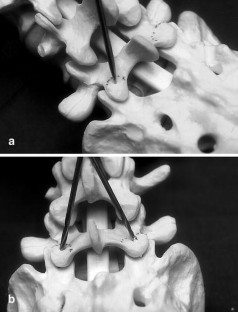

Fig. 2. a